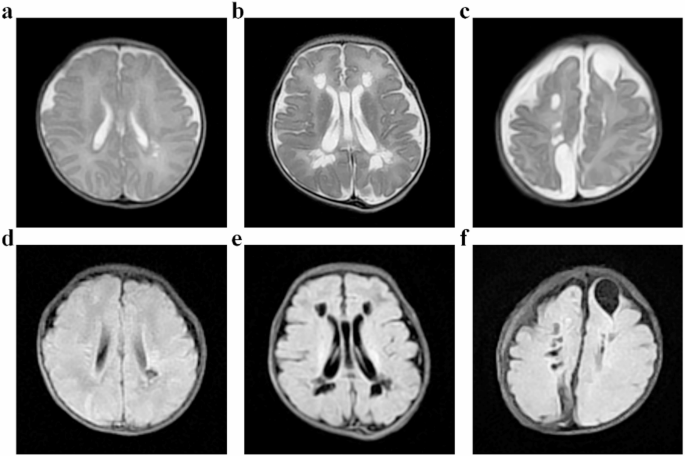

Lee, Y. A. White matter injury of prematurity: its mechanisms and clinical features. J. Pathol. Transl Med. 51 (5), 449–455 (2017).